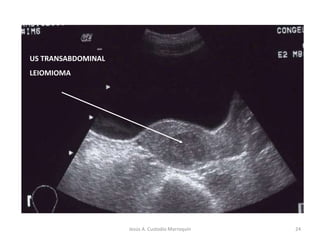

ULTRASONIDO INTRAVAGINAL O ABDOMINAL

• Método más altamente fiable en el diagnóstico de estas

lesiones

• Diagnostico de tumores intramurales o subserosos

Diagnóstico

US TRANSABDOMINAL

LEIOMIOMA